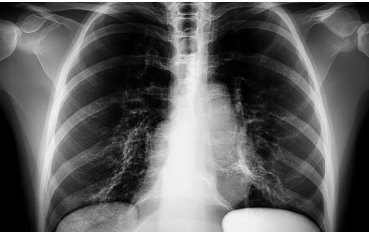

폐렴 예방을 위한 생활 수칙

폐렴은 적절한 예방으로 충분히 막을 수 있는 질환입니다. 다음과 같은 생활 수칙을 지키는 것이 중요합니다.

- 정기적인 폐렴 예방접종 (특히 노인, 만성질환자)

- 손 씻기 등 개인 위생 철저히

- 금연, 건강한 식습관, 충분한 수면

- 면역력 강화를 위한 운동 및 영양 섭취

폐렴 치료 시 꼭 지켜야 할 사항

- 항생제는 끝까지 복용해야 합니다. 증상이 호전되어도 남은 약을 중단하면 재발하거나 내성이 생길 수 있습니다.

- 기침은 무조건 억제하지 마세요. 기침은 폐 속 이물질과 가래를 배출하는 기능이므로, 심하지 않다면 억제제를 남용하지 않는 것이 좋습니다.

- 흡연과 음주는 피해야 합니다. 폐 기능을 저하시키고 회복을 더디게 만듭니다.

- 자가치료는 금물입니다. 열이 계속되거나 호흡곤란이 생기면 즉시 병원을 찾아 정확한 진단을 받아야 합니다.

조기 대응이 핵심입니다

폐렴 증상은 단순한 감기처럼 가볍게 시작되지만, 제때 치료하지 않으면 폐 기능 저하나 심각한 전신 합병증으로 이어질 수 있습니다. 따라서 초기 신호를 놓치지 않고 빠르게 대응하는 것이 회복 속도에 큰 차이를 만듭니다. 증상이 나타났을 때는 스스로 판단하기보다 의료진의 진단을 통해 정확한 상태를 확인하고, 상황에 맞는 치료를 받는 것이 바람직합니다. 또한 평소에도 면역력을 잘 관리하고 개인 위생에 신경 쓰는 것이 폐렴 증상을 예방하는 데 매우 중요합니다. 혹시라도 기침, 열, 호흡 곤란 등 의심되는 증상이 지속된다면 망설이지 말고 가까운 병원을 방문해보세요. 건강한 호흡은 건강한 삶의 시작입니다. 지금의 작은 실천이 내일의 큰 안정을 만들어 줍니다.